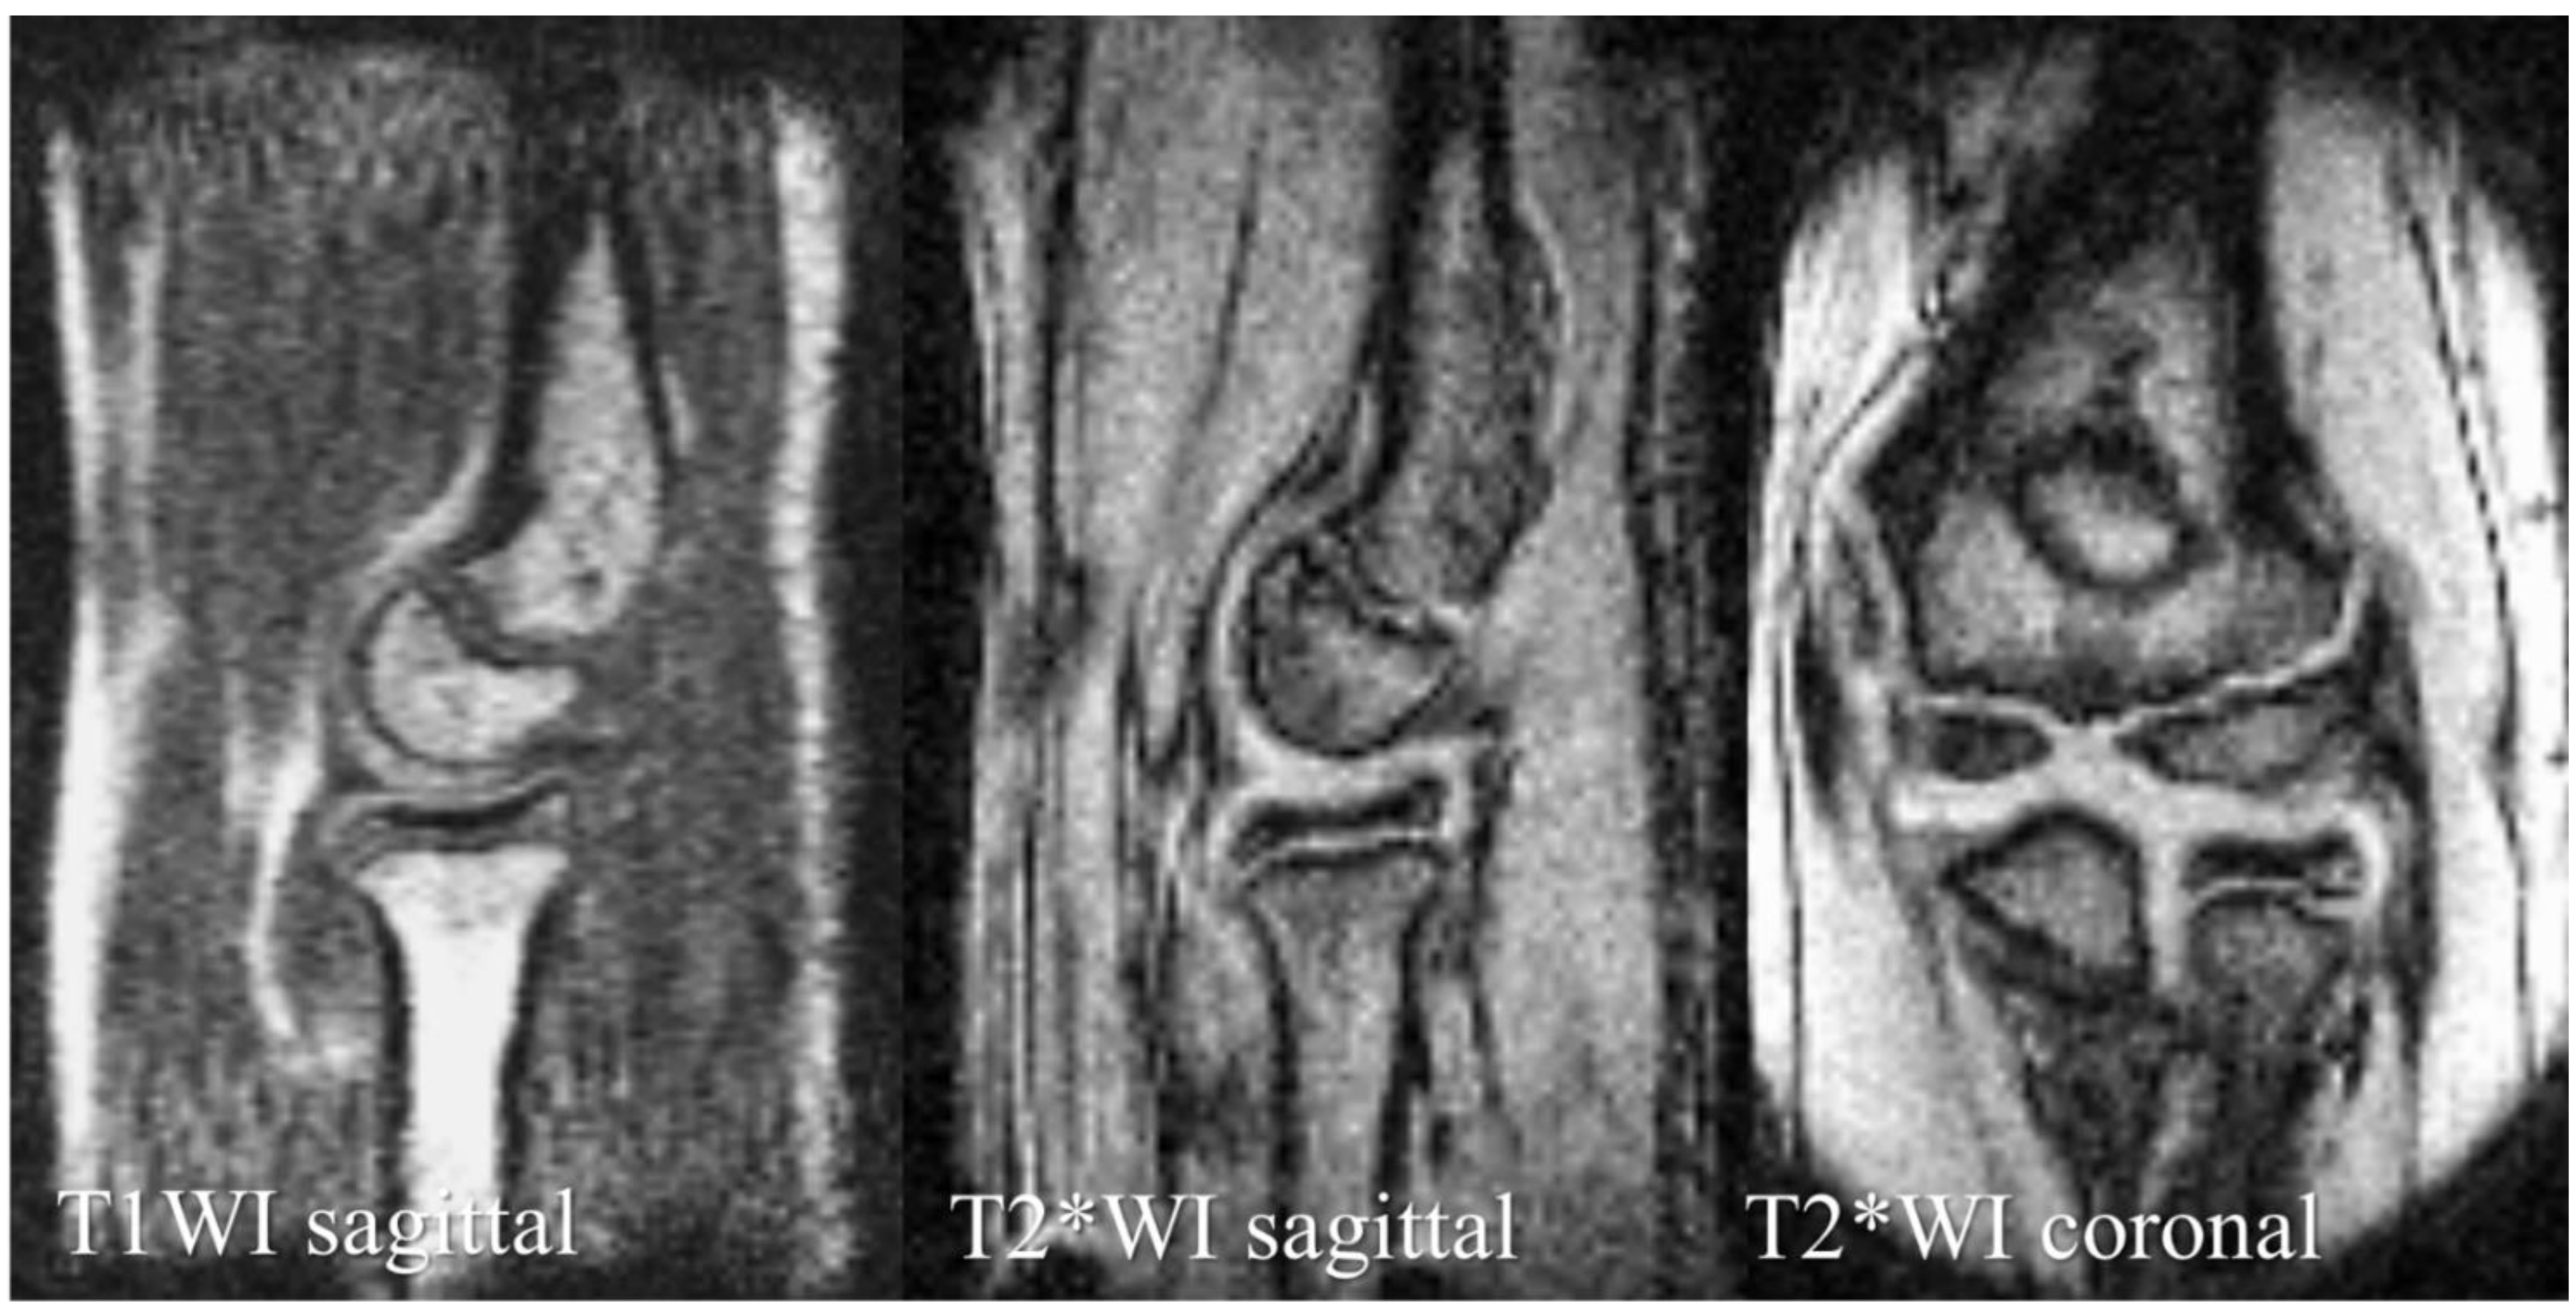

| Sequence Type | T1WI | T2*WI | T2*WI |

|---|---|---|---|

| Image plane | Sagittal | Sagittal | Coronal |

| FOV | 180 × 120 × 90 mm3 | 180 × 180 mm2 | 180 × 180 mm2 |

| Matrix size | 256 × 128 × 32 | 256 × 192 | 256 × 192 |

| Slice thickness, mm | - | 3 | 3 |

| TR, ms | 40 | 500 | 500 |

| TE, ms | 4 | 16 | 16 |

| Flip angel | 60° | 75° | 75° |

| Scan time | 1 min 22 s | 1 min 38 s | 1 min 38 s |